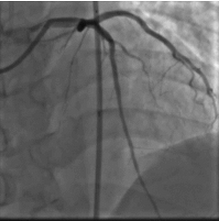

造影结果

2015年10月23日:左主干远段30%狭窄;左前降支近段支架自开口完全闭塞;左回旋支中段长病变,狭窄40%~50%,高位钝缘支粗大,未见狭窄(图1)。右冠粗大、优势型,近段管壁不规则,左室后支、后降支未见狭窄(图2、3)。

图2、3